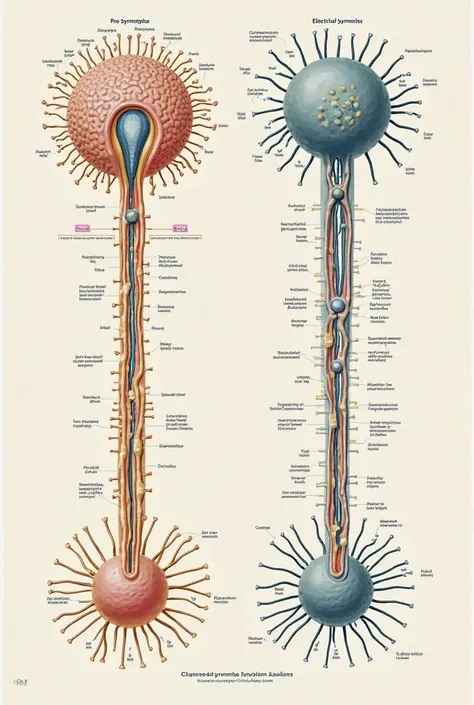

A diagram of the anatomy of the human body

Realice un dibujo de la piel. Coloque las siguientes referencias: Epidermis Fermis Hypodermis Keratinized squamous stratified epithelium Hair Sebaceous gland Sweat gland Pilo erector muscle Connective tissue Blood vessels Nerves Adipocytes

Epidermis Fermis Hypodermis Keratinized squamous stratified epithelium Hair Sebaceous gland Sweat gland Pilo erector muscle Connective tissue Blood vessels Nerves Adipocytes